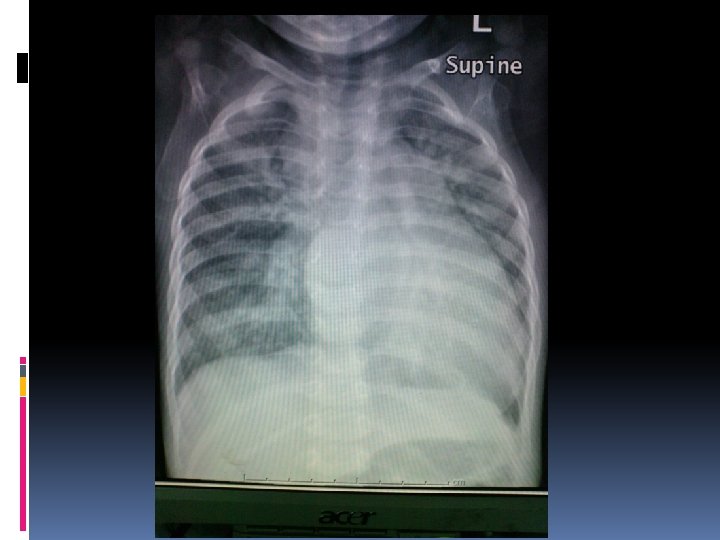

Case II 1 -y-2 -mo-old boy Cyanotic since birth Systolic ejection murmur gr 4/6 at LPSB

Investigation Echocardiography truncus arteriosus type I with moderate truncal valve regurgitation Cardiac catheterisation truncus arteriosus type I with PHT PVR 6 Woods unit

Findings and procedure Truncus type I, right sided aortic arch RPA & LPA 10 mm Tricuspid truncal valve with regurgitation due to redundancy of posterior truncal cusp Rastelli operation (using 13 mm pulmonary homograft)